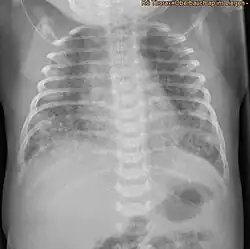

Síndrome de aspiração de mecônio

A síndrome de aspiração de mecônio (português brasileiro) ou síndrome de aspiração de mecónio (português europeu) (MAS), também conhecida como aspiração meconial é uma condição médica que afeta recém-nascidos. Este problema clínico descreve a fisiopatologia do líquido amniótico corado com mecônio e a presença deste nos pulmões. Desse modo, compreende-se que o mecônio tem um alto índice de gravidade, dependendo de quais condições e complicações se desenvolvem após o parto. Além disso, a fisiopatologia é multifatorial e extremamente complexa, razão pela qual é a principal causa de morbimortalidade em bebês.[1][2]